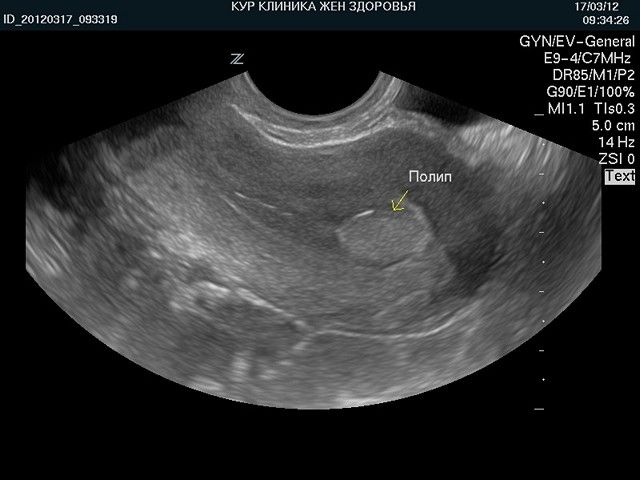

Врачи отмечают, что полипы в матке и эндометрии на УЗИ могут выглядеть как гиперэхогенные образования, которые имеют четкие контуры. Эти образования могут быть одиночными или множественными, и их размеры варьируются от нескольких миллиметров до нескольких сантиметров. При наличии кровотока, что часто определяется с помощью цветного допплеровского картирования, полипы могут демонстрировать усиленное кровоснабжение, что указывает на их активность и потенциальную возможность злокачественного перерождения. Важно, что наличие кровотока не всегда свидетельствует о патологии, однако требует внимательного наблюдения и, при необходимости, дальнейшего обследования. Врачи подчеркивают, что правильная интерпретация УЗИ-данных и комплексный подход к диагностике являются ключевыми для выбора оптимального метода лечения.

Как выглядят полипы на снимке УЗИ?

Ультразвук – это волны, которые при отражении формируют картинку. Жидкости поглощают излучение и являются анэхогенными, выглядят темным пятном. Чем плотнее структура, тем более она эхогенна и светлее. По таким характеристикам можно определить тип ткани, например, кость высвечивается белым и называется гиперэхогенной. Киста с жидким содержимым будет круглым темным пятном с четкими краями.

Некоторые признаки, характеризующие патологию при УЗИ:

- Хорошо различимые границы;

- Грибообразная или круглая структура;

- Полость матки расширена, как и цервикальный канал;

- Деформация контура органа;

- Кисты эндометрия вокруг основания полипа.

Железистые образования, как менее плотные смотрятся более темными, чем фиброзные. По тому, как выглядят полипы эндометрия на снимке, невозможно точно определить их разновидность.

Признаки полипа эндометрия в матке на УЗИ. Полип матки на УЗИ выглядит как новообразование с четким контуром. Другим его признаком может стать расширение полости и утолщение стенки матки. Для диагностики новообразований лучше всего подходят 5-7 дни менструального цикла.